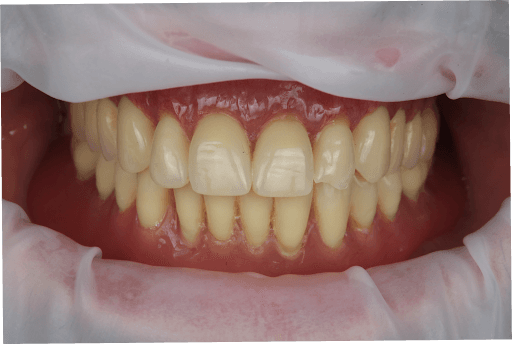

3.6 Clinical Delivery of the Temporary Full-Arch Implant-Supported Appliances

The temporary MUA screw-retained prosthesis were installed in the patient's mouth and occlusion was checked. From the clinical perspective, occlusal contacts required minimal correction as the occlusion was already accurately planned in the CAD software. The patient expressed comfort and reported to be satisfied with the esthetic outcome.

A carefully controlled occlusal scheme with reduced posterior contacts was adopted to minimize overload during osseointegration. The patient was instructed to follow a soft diet during the initial healing phase.

Occlusion check of upper All-on-X appliance

Occlusion check of lower All-on-X appliance

Occlusion check of All-on-X appliance

Upper, lower, and occlusion check of the temporary full-arch implant-supported appliances.

Close-up photo of immediate clinical outcome

Full-face photo of immediate clinical outcome

Immediate clinical outcome